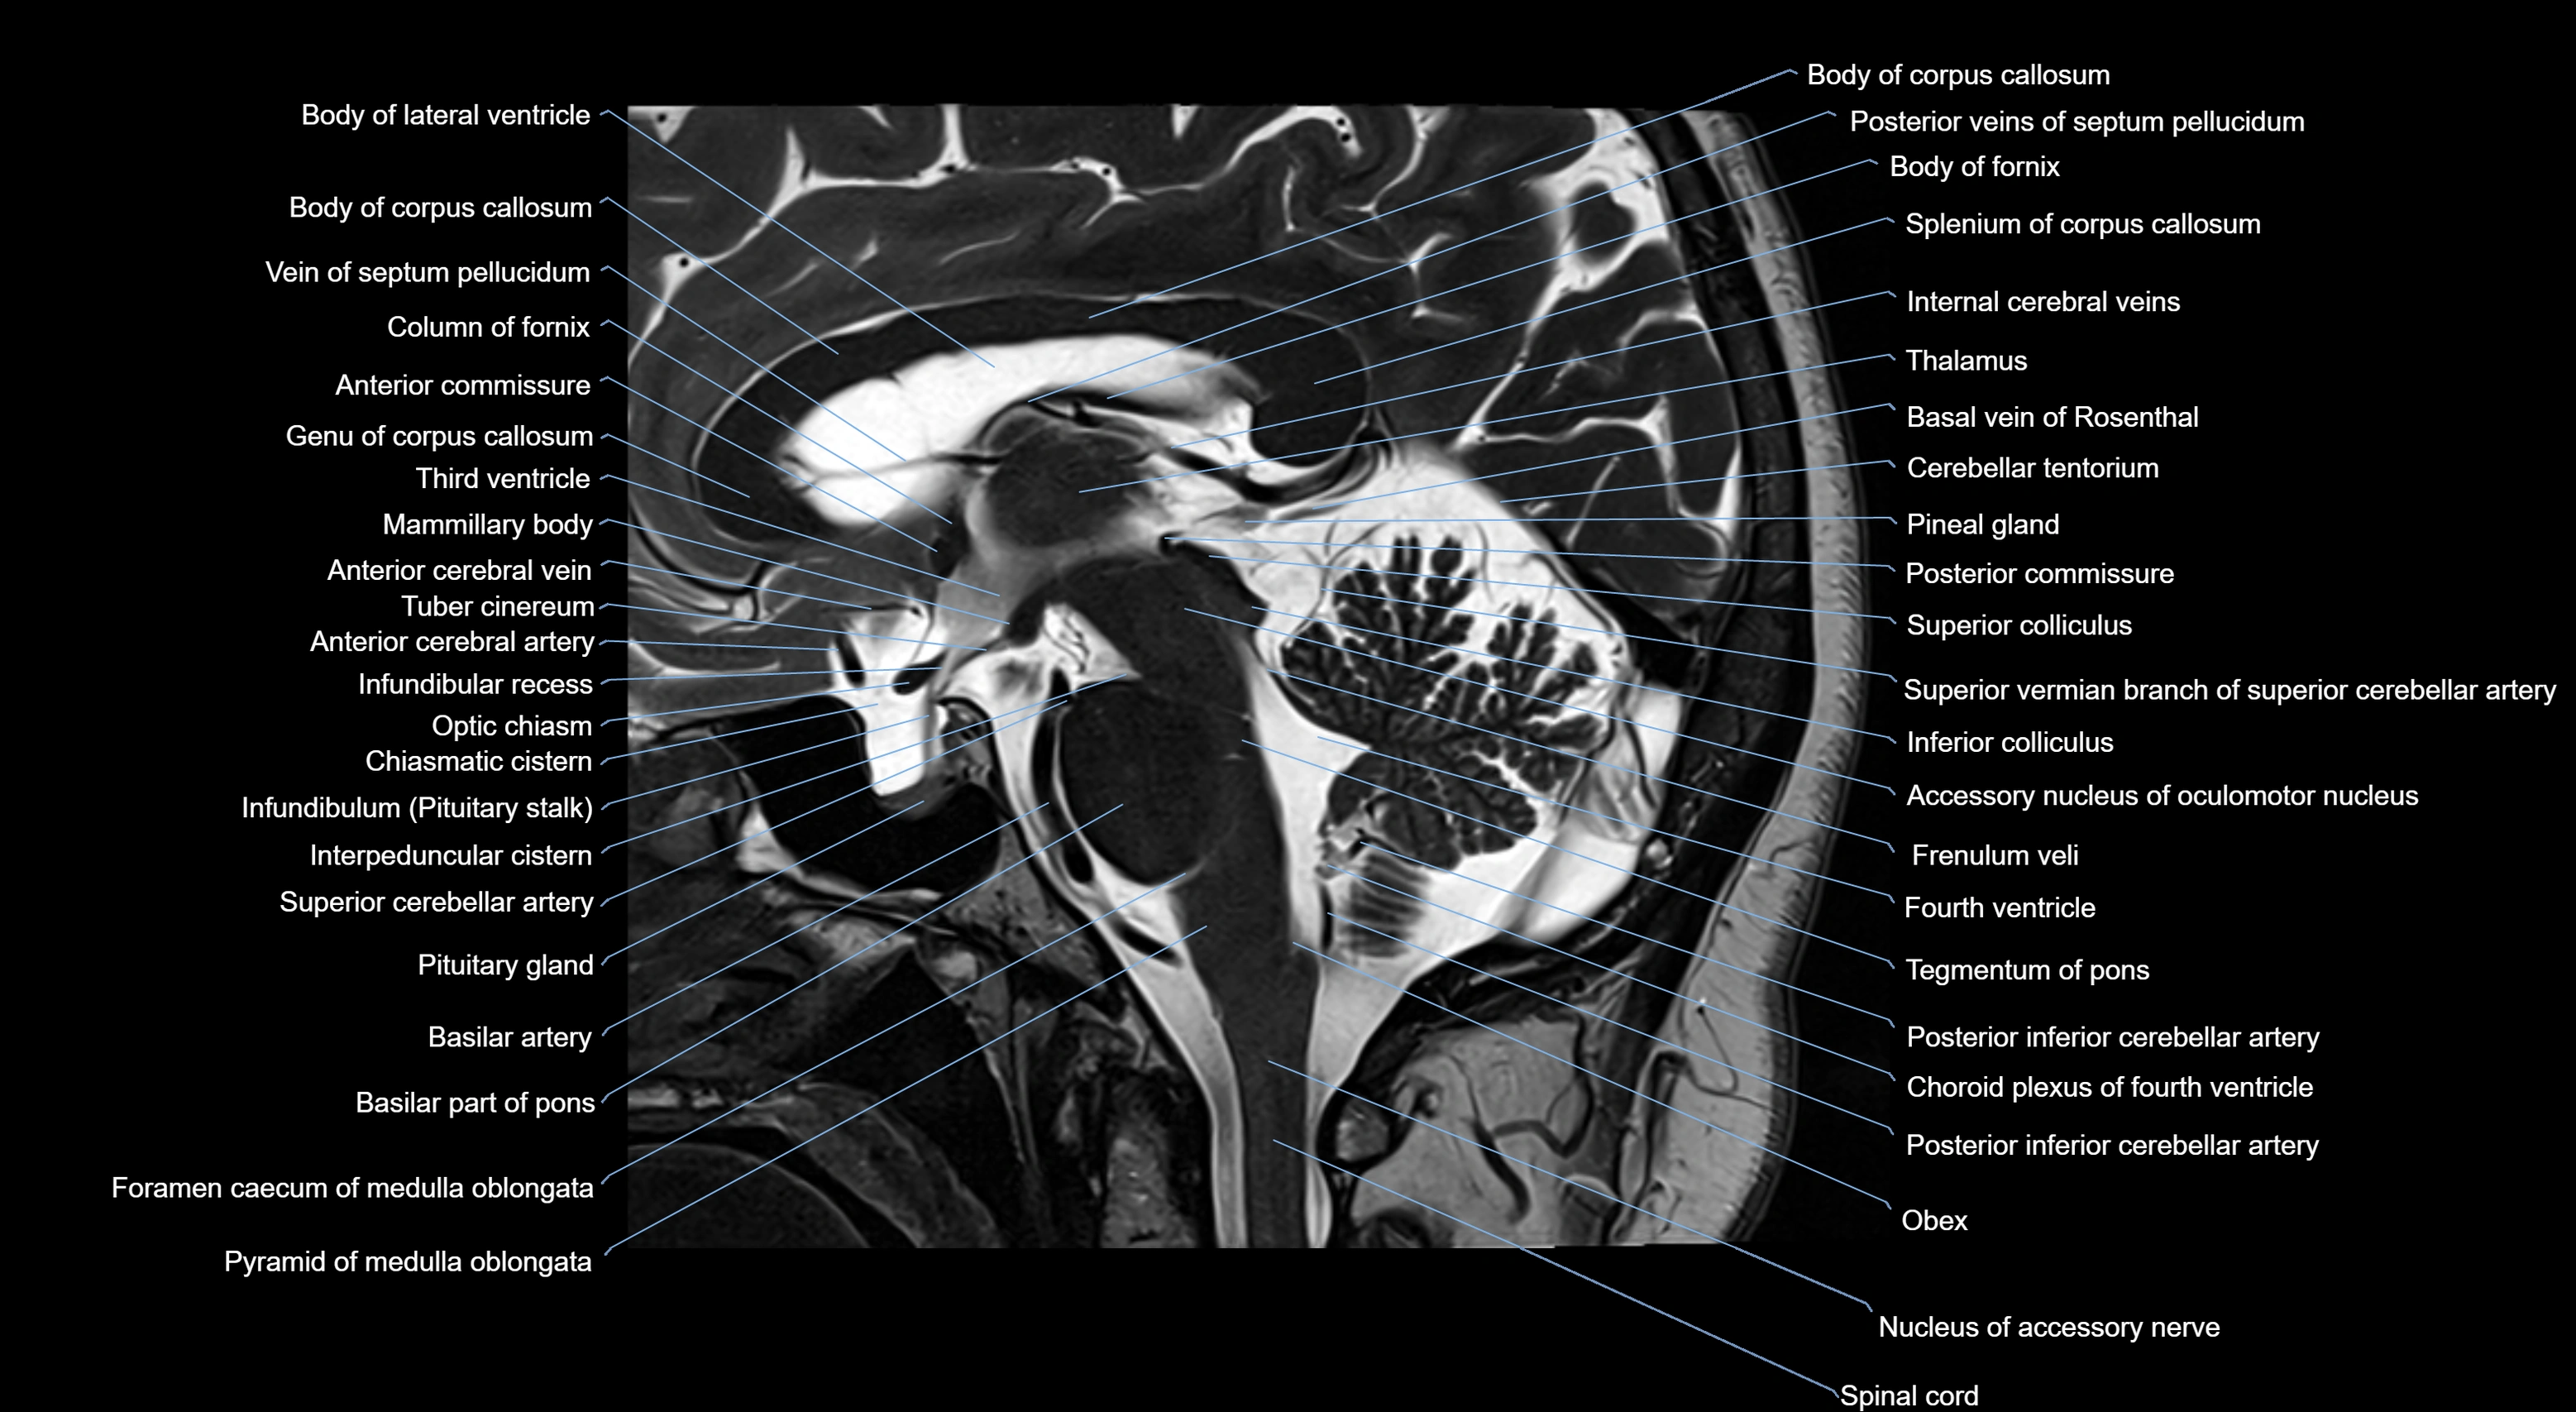

MRI images